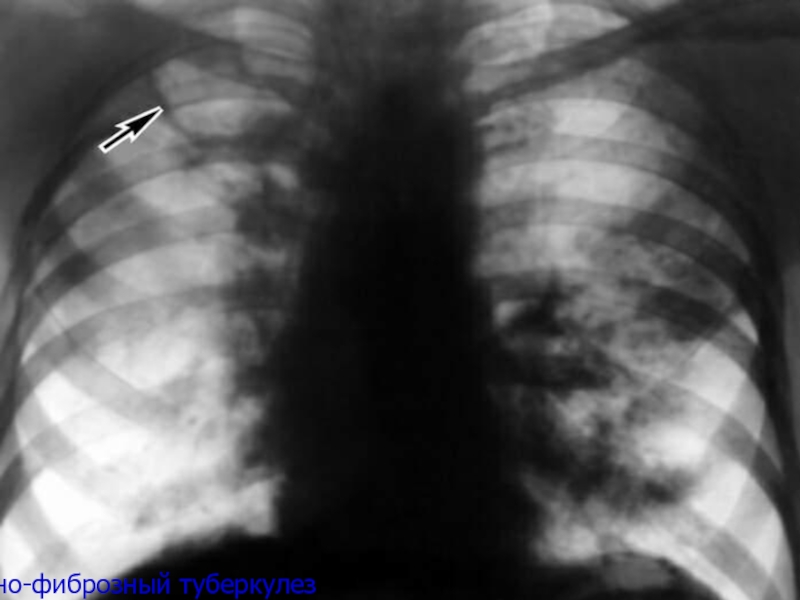

Слайд 40Кавернозно-фиброзный туберкулез

Кавернозно-фиброзный туберкулез